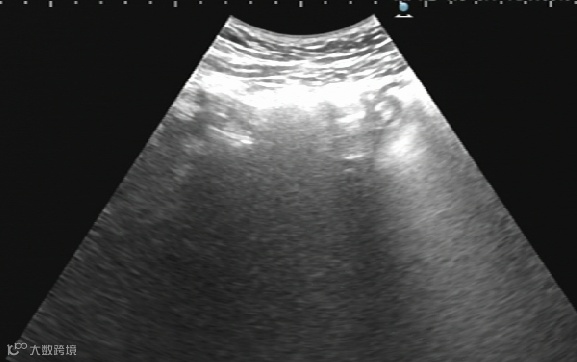

卵巢巧克力囊肿硬化治疗:

治疗前

治疗后